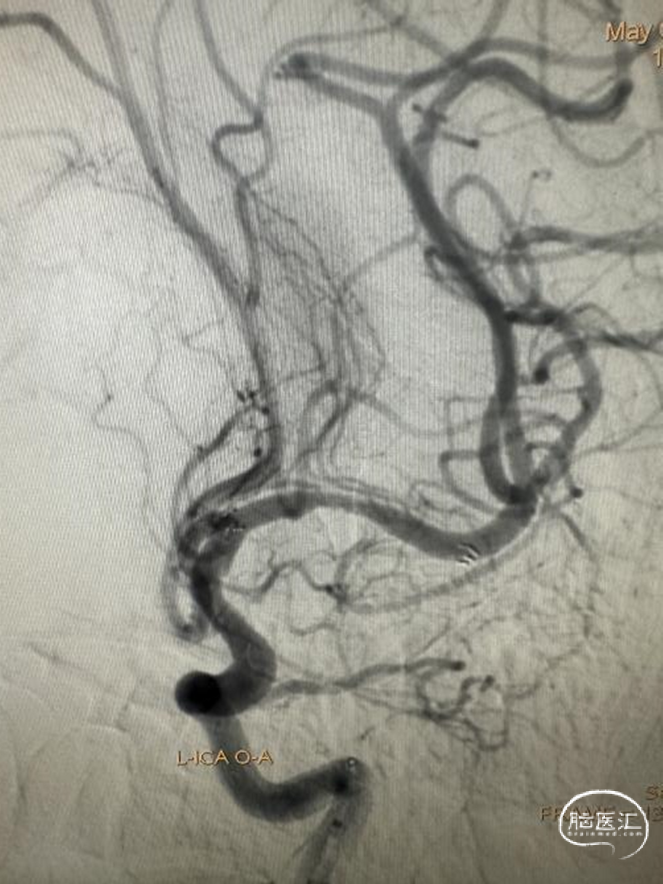

DSA

左侧大脑中动脉重度狭窄,近端:1.78mm,远端:2.18mm,最窄:0.25mm,长度:14.70mm,狭窄率约:89%。

患者麻醉复苏后无神经功能障碍。患者术后标准正侧位造影。